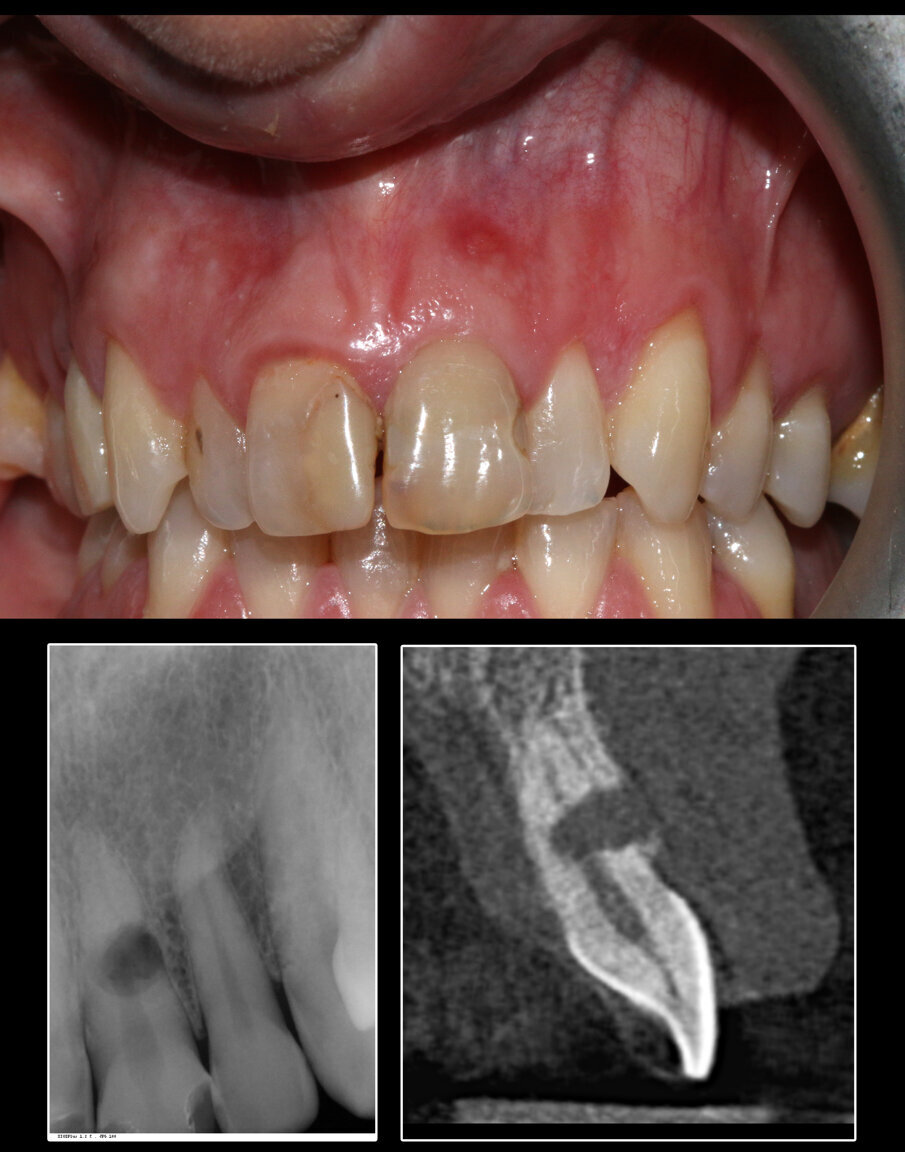

Il trattamento con SST di elementi dentari affetti da riassorbimento radicolare esterno rimane un’indicazione controversa: parrebbe teoricamente rischioso mantenere una piccola quota di radice vestibolare su un elemento dentario che sia già stato oggetto di rimaneggiamento per opera di cellule clastiche di origine ossea. Tuttavia, anche in base alle esperienze maturate in questi anni dall’Autore e dagli altri soci fondatori della SISS, il riassorbimento radicolare esterno rimane una controindicazione alla tecnica quando questo riguardi l’aspetto vestibolare della radice (Figg. 1, 2). Se il processo patologico rimane confinato sull’aspetto palatino o linguale, la tecnica può essere messa in atto, con il vantaggio finale di mantenere tutti i volumi sull’aspetto vestibolare: margine gengivale, bozze radicolari, gengiva cheratinizzata e papille.

Il caso presentato riguarda una paziente di 62 anni, senza patologie degne di nota, già trattata presso altri studi professionali con una serie di riabilitazioni protesiche su monconi (corone singole). Nel 2021, si presenta alla nostra osservazione lamentando dolenzia costante sull’elemento 3.3 canino inferiore di sinistra, vitale e già rivestito con una corona in ceramica.

L’esame di primo livello (radiografia endorale) mostra la presenza di un minus dei tessuti calcificati a carico della radice. Si impone per ovvie ragioni un approfondimento volumetrico 3D: soltanto una CBCT ci consentirà di localizzare correttamente la lesione e valutarne la posizione, l’estensione e l’eventuale recuperabilità dell’elemento dentario. Il taglio trasversale della radiografia 3D mostra un riassorbimento radicolare esterno che riguarda la porzione linguale dell’elemento dentario (Figg. 1-4). Il riassorbimento presenta una posizione particolarmente sfavorevole, in quanto si estende già al di sotto del margine osseo crestale su un elemento dentario peraltro già trattato da un punto di vista protesico (Figg. 2, 3). Le opzioni terapeutiche proposte alla paziente sono sostanzialmente due: trattamento endodontico e rifacimento del restauro protesico, previo accesso chirurgico sul lato linguale con allungamento di corona clinica, oppure impianto post-estrattivo con tecnica Socket-Shield. La paziente sceglie questa seconda opzione e firma regolare consenso informato.

Fig. 1_Esempio di elemento dentario affetto da riassorbimento radicolare esterno non candidabile a SST: la lesione riguarda esattamente l’aspetto vestibolare, tanto da compromettere anche l’integrità del piatto osseo buccale.

Fig. 3_Il caso clinico descritto: elemento 3.3 già rivestito di corona protesica, vitale e dolente.